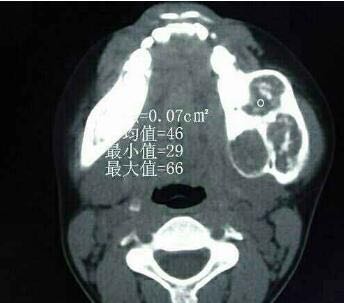

患者性别:男 患者年龄:12岁 患者病史:2月前被其哥发现左下颌肿胀,无明显不适,肿物缓慢生长。 患者症状:无明显症状

检查及结果: 颌面部左右不对称,左下颌后1|3明显膨隆,可触及鸡蛋大肿物,质硬,局部黏膜无红肿,张口度及张口型正常,CT提示:良性肿物